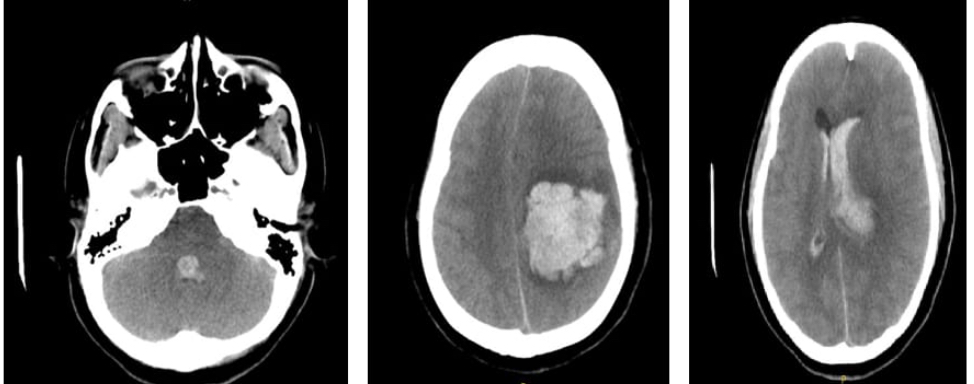

Case Description: A 31-year-old pregnant patient at her 12 weeks of  gestation was admitted. We reported her history of headache, vomiting and acute loss of consciousness. Presenting with GCS 3/15 on arrival, unequal, non-reactive pupils on physical examination, she was intubated because of low GCS and impaired respiratory function. Imaging scans revealed a thalamic hematoma on the left side of large size as well as extensive brain edema and signs of herniation of the brain. Emergency decompressive craniectomy was carried out in a bid to lower intracranial pressure. Because of the patient's pregnancy, an apnea test was not possible as it was a risk to fetal health. The patient also had a craniectomy which made it impossible to use an EEG to determine brain function. A CT angiogram was necessary to rule out vascular causes which was not conducted because there was a high risks of radiation exposure to the fetus.